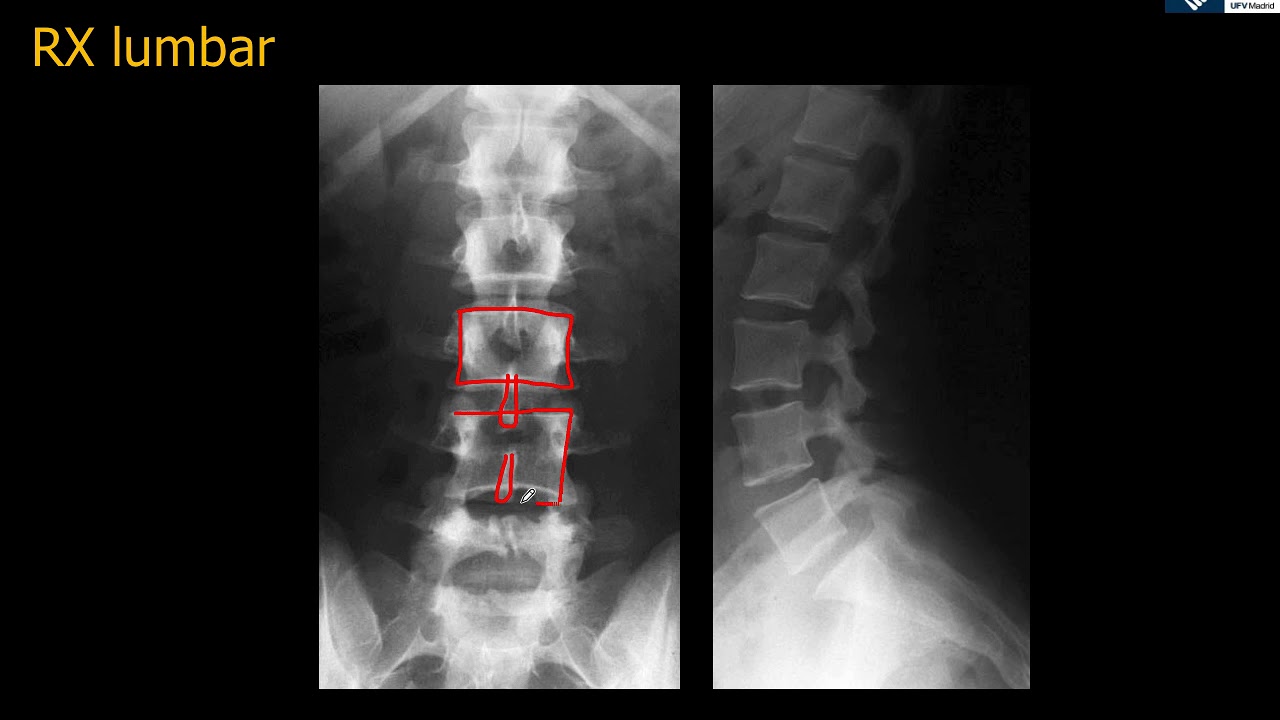

Una radiografía de espalda, también conocida como radiografía lumbar o cervical, es una imagen que captura la estructura ósea de tu columna vertebral. Al igual que tomar una fotografía instantánea de un edificio, las radiografías nos permiten ver los componentes internos de la columna, tales como los huesos, articulaciones y, en ocasiones, los tejidos blandos cercanos. Se utiliza principalmente para diagnosticar condiciones como fracturas, curvaturas anormales de la columna (como la escoliosis) o patologías degenerativas como la artritis.

¿Qué se Observa en una Radiografía de Espalda?

Ahora bien, vamos al grano: ¿qué es lo que realmente vemos en estas imágenes? La radiografía de espalda nos muestra:

La primera y más obvia cosa que puedes notar son los huesos vertebrales. La columna vertebral se compone de 33 vértebras, y en la radiografía, se observarán como estructuras blancas que se alinean en el centro de tu imagen. Cada vértebra tiene un cuerpo vertebral redondeado que es responsable de soportar el peso y las vértebras se separan entre sí por discos intervertebrales, que normalmente solo se ven como sombras.

Las radiografías también permiten a los médicos evaluar la curvatura de la columna. Por ejemplo, si hay un aumento en la curvatura hacia adelante (cifosis) o hacia atrás (lordosis), se podrá observar fácilmente. Y, por supuesto, si hay signos de escoliosis – una curvatura lateral anormal – también se reflejará en las imágenes.

Las articulaciones entre las vértebras son otro aspecto importante. La radiografía puede mostrar si hay signos de desgaste o inflamación. Además, se pueden ver los espacios intervertebrales donde se encuentran los discos intervertebrales, que actúan como amortiguadoras entre las vértebras. Un espacio estrecho puede indicar degeneración o enfermedad del disco.